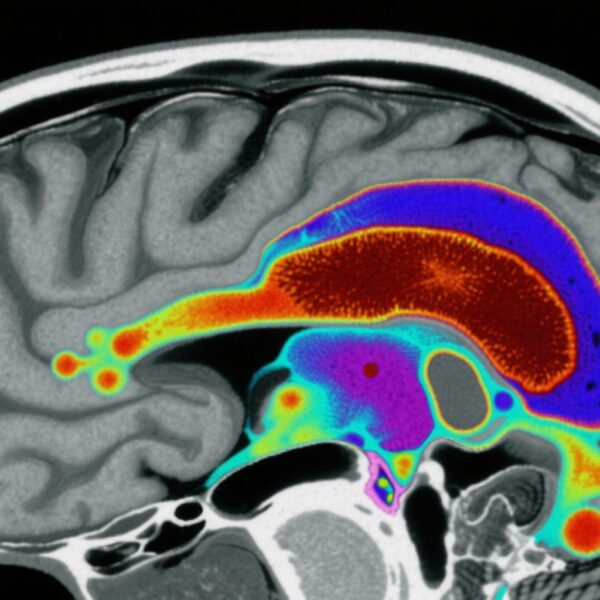

This investigation utilized data from the Mental and Substance Use Disorders Prevalence Study, a nationally representative household sample of nonelderly US adults (N=4,764). Participants underwent clinician-administered Structured Clinical Interview for DSM-5 (SCID-5) assessments to determine past-year and lifetime prevalence of SSDs, including schizophrenia, schizoaffective disorder, and schizophreniform disorder, as well as to identify positive psychotic symptoms.